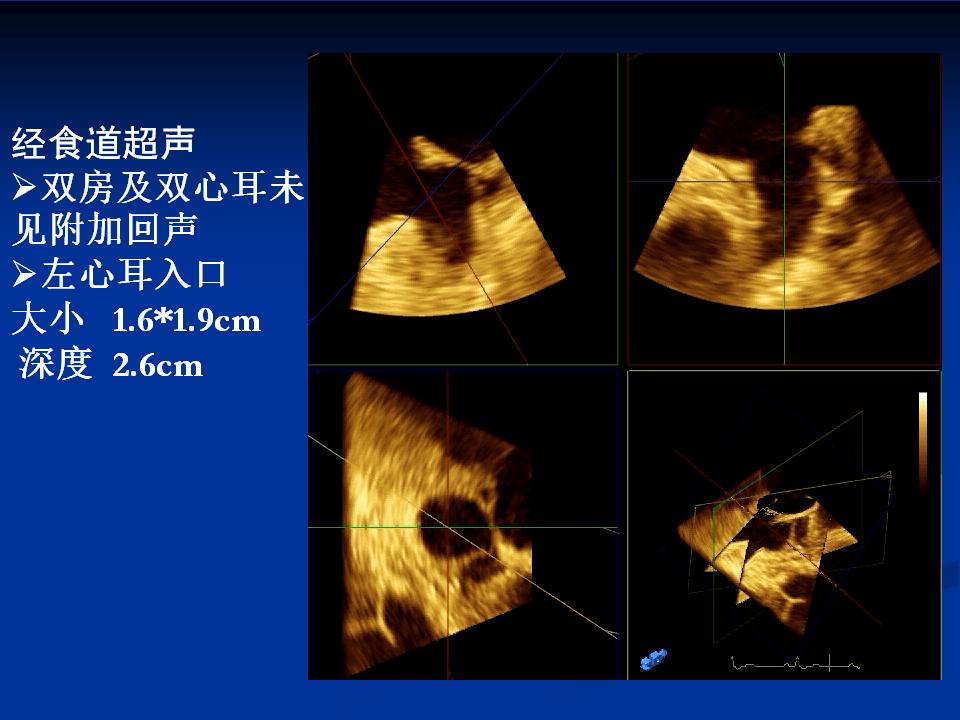

心房颤动伴多发脑梗塞、抗凝出血1例